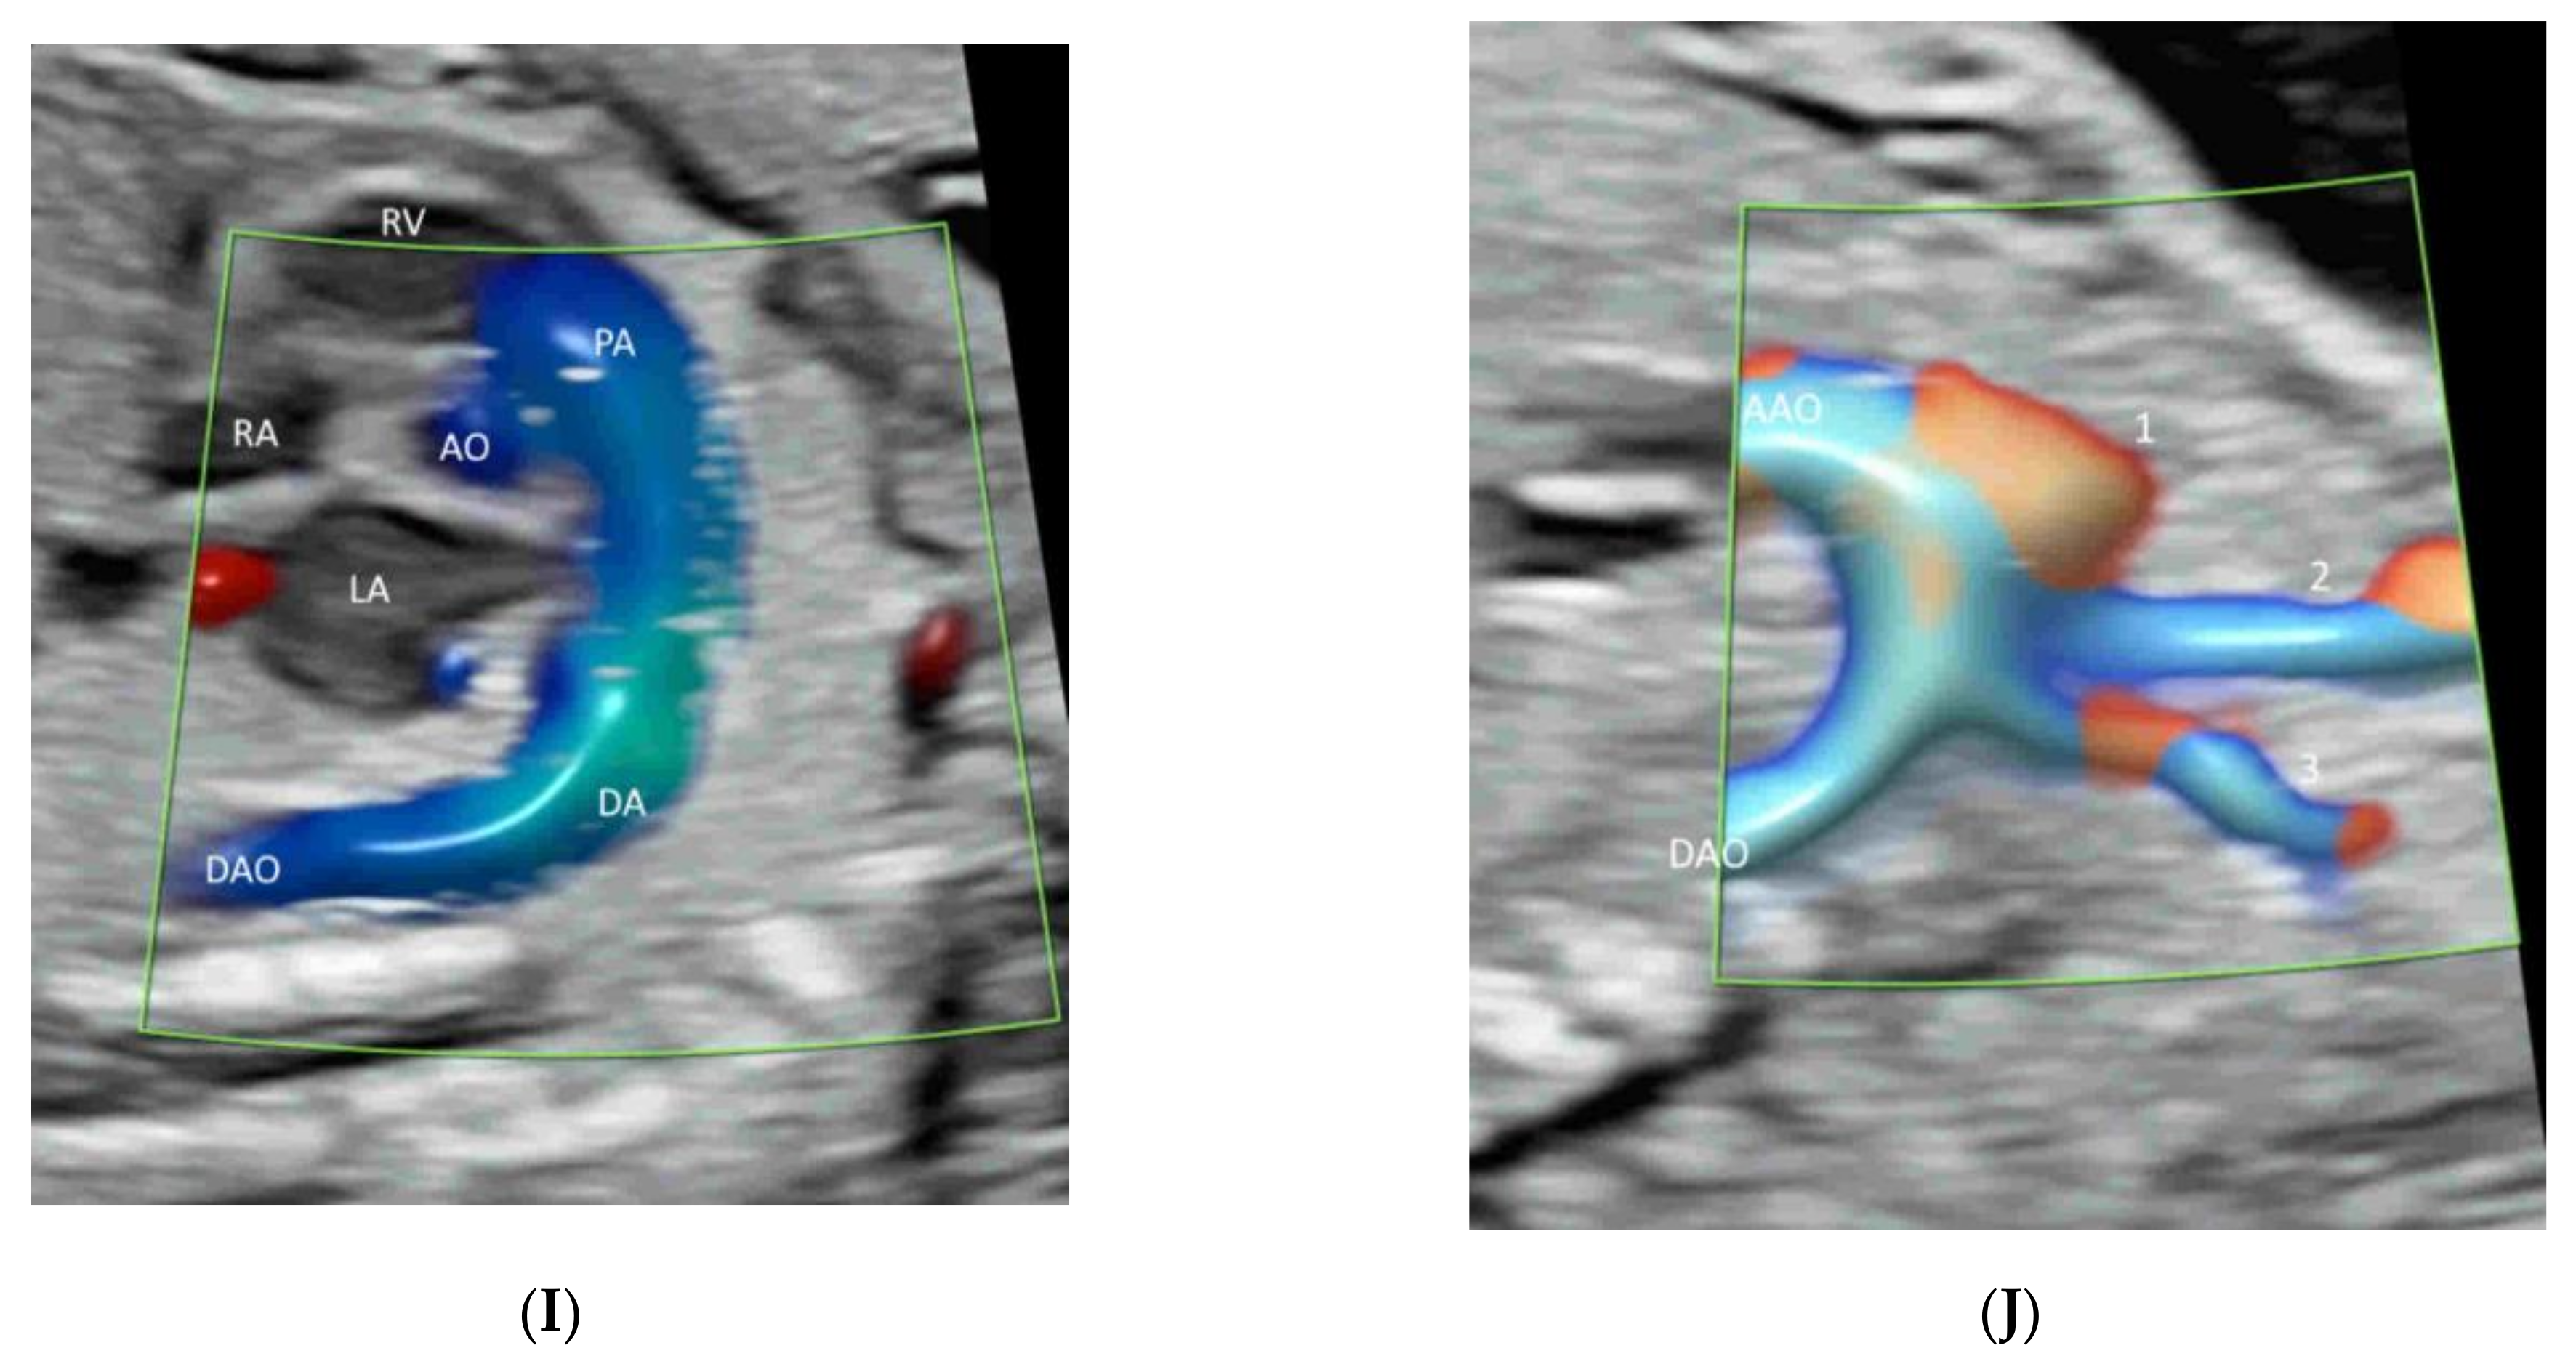

- Yagel, S.; Cohen, S.M.; Valsky, D.V.; Shen, O.; Lipschuetz, M.; Messing, B. Systematic examination of the fetal abdominal precordial veins: A cohort study. Ultrasound Obstet. Gynecol. 2015, 45, 578–583. [Google Scholar] [CrossRef] [Green Version]

- Yagel, S.; Cohen, S.M.; Valsky, D.V. Simplifying imaging of the abdominal fetal precordial venous system. Ultrasound Obstet. Gynecol. 2019, 53, 571–575. [Google Scholar] [CrossRef]

- Leung, K.Y. Imaging of fetal precordial venous system by four-dimensional ultrasound with spatiotemporal image correlation technology. J. Clin. Ultrasound 2021. [Google Scholar] [CrossRef]